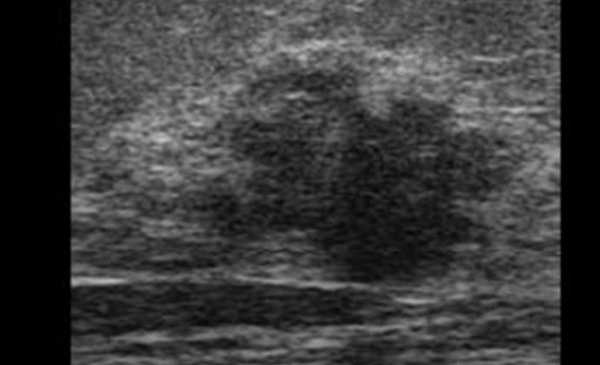

УЗИ мягких тканей бедра и голени

Ультрасонографию нижних конечностей в большинстве случаев рекомендуют пациентам с подозрением на травматические повреждения и инфекционно-воспалительные процессы. Также УЗИ применяют в комплексной диагностике злокачественных опухолей, локализующихся не только в длинных трубчатых костях обсуждаемой области, но и в прилежащих мягких тканях.

Ультразвуковое сканирование мягких тканей нижних конечностей используют и при посттравматических осложнениях, связанных с повреждениями суставных элементов, чаще в зоне тазобедренных сочленений. Последствия переломов вертлужной впадины и верхней трети бедренной кости проявляются в виде контрактур. УЗИ позволяет изучить структурные изменения в близлежащих мышечных волокнах. Последние на стороне поражения имеют меньшую толщину в сравнении с неизмененным сегментом.